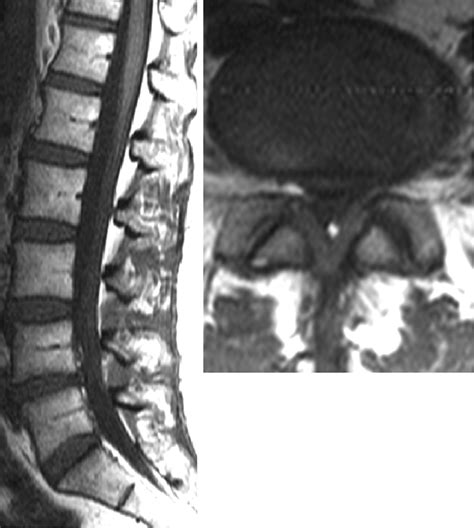

MRI (Magnetic Resonance Imaging) Offers detailed images of the spine, including soft tissues, and is often the preferred method for diagnosing ligamentum flavum hypertrophy.

• ligamentum flavum hypertrophy on mri

• ligamentum flavum hypertrophy radiology